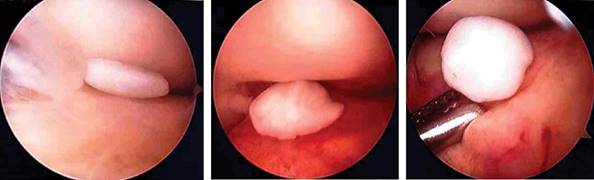

Mujer de 55 años de edad, refiere caída de su propia altura sobre rodilla izquierda presentando dolor moderado en la región anterolateral y limitación funcional, como único antecedente: múltiples microtraumatismos previos en rodilla. Se le solicita resonancia magnética simple (Figura 1) identificando imagen característica de condromatosis sinovial, después se realiza artroscopia con resección de fragmentos condrales libres (Figura 2), sin observar cambios en tejido sinovial y se envían a patología, confirmando la alteración (Figura 3).

La condromatosis de localización inframeniscal, como el caso presentado, son los más difíciles de detectar vía artroscópica, en especial cuando son pequeños, por lo que se recomienda realizar una exploración cuidadosa para la extracción total de fragmentos.